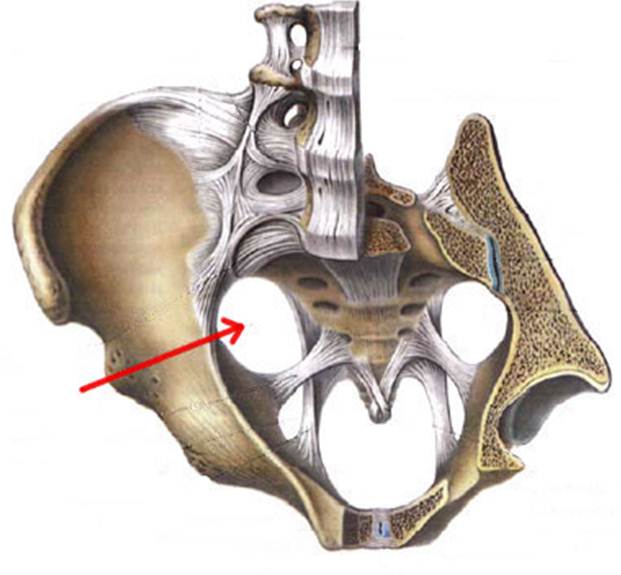

S: Стрелка указывает на zona orbicularis

S: Стрелка указывает на lig. Ischiofemorale

S: Стрелки указывают на lig. iliofemorale

S: Стрелка указывает на lig. pubofemorale

S: Стрелка указывает на labrum acetabuli

S: Стрелка указывает на lig. Capitis femoris

S: Стрелка указывает на facies lunata